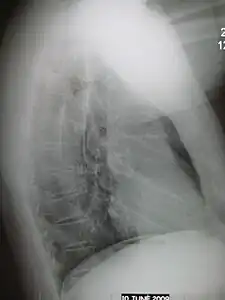

Normal AP CXR

Normal lateral CXR